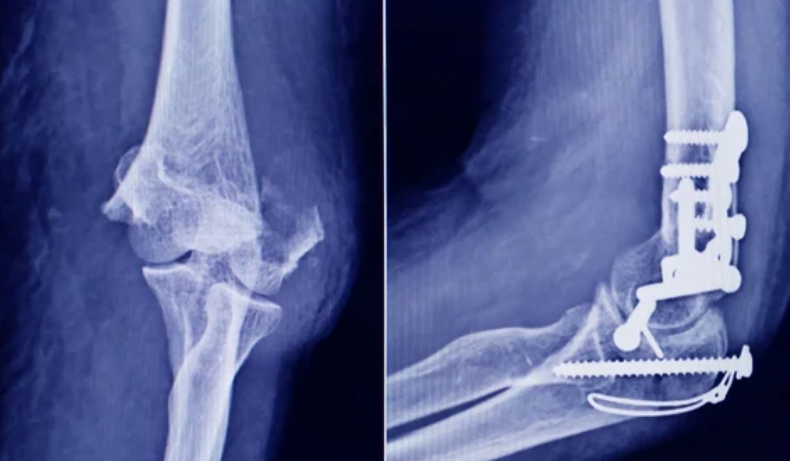

La Administración Nacional de Medicamentos, Alimentos y Tecnología Médica (ANMAT) advirtió a la población por un tornillo utilizado en cirugías traumatológicas debido a que es falso, por lo que su uso representa riesgo para la salud del paciente al que se lo implante.

Se trata de un tornillo utilizado en cirugías traumatológicas que fue detectado durante una inspección de control de mercado realizada en una ortopedia ubicada en la ciudad de San Miguel de Tucumán.

Dicho tornillo es producido por la firma Stryker Corporation, que se encuentra registrada ante ANMAT bajo el PM 594-139. Luego de la inspección, se exhibió la muestra recolectada ante la responsable técnica de dicha empresa, quien afirmó que se trataba de un producto falsificado.

Las autoridades de la ANMAT dieron a conocer las características del producto para su advertencia: STRYKER 10 mm X 28 mm – BIOABSORBABLE – ACL INTERFERENCE SCREW – REF 234-010-067 – LOT 90905.